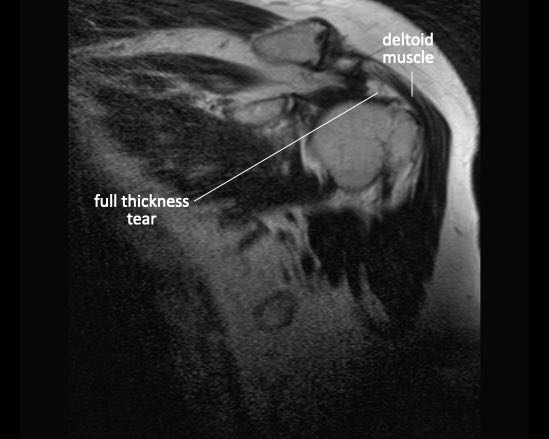

Rách toàn bộ chiều dày

Rách toàn bộ chiều dày (Full Thickness Tear – FTT) là tổn thương kéo dài từ mặt túi hoạt dịch (bursal surface) xuyên suốt đến mặt khớp (articular surface).

Rách toàn bộ chiều dày không hoàn toàn

Dấu hiệu đặc trưng trên MRI của rách toàn bộ chiều dày không hoàn toàn là khe hở chứa đầy dịch trên chuỗi xung T2W.

Tuy nhiên, đôi khi khe hở trong gân có thể chứa đầy mảnh vụn hoặc mô hạt, và tín hiệu sẽ không tương đương với tín hiệu của nước.

Các dấu hiệu hình ảnh là gì?

Có hình ảnh rách toàn bộ chiều dày phần trước của gân cơ trên gai, kéo dài từ mặt khớp đến mặt túi hoạt dịch.

Do các sợi gân phía sau của gân cơ trên gai còn nguyên vẹn, tổn thương này được gọi là rách toàn bộ chiều dày không hoàn toàn của gân cơ trên gai.

Không có co rút.

Rách toàn bộ chiều dày hoàn toàn

Có hình ảnh rách toàn bộ chiều dày gân cơ trên gai kèm co rút và teo cơ.

Lưu ý các dải mỡ trong cơ tròn bé, cơ trên gai và cơ dưới gai.

Các vị trí rách toàn bộ chiều dày thường gặp nhất bao gồm:

- Cơ trên gai (Supraspinatus)

Rách phần trước xa của gân cơ trên gai là vị trí thường gặp nhất.